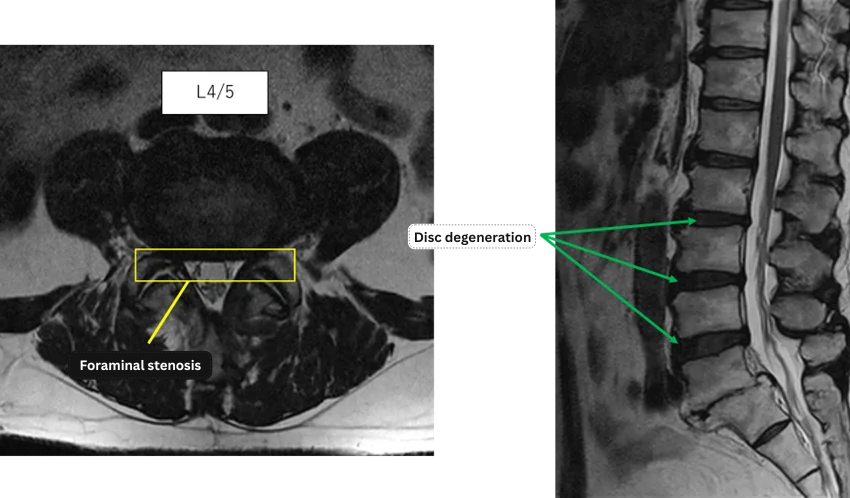

L1/2: No anomalies.

L2/3: Degenerative disc disease.

L3/4: Degenerative disc disease.

L4/5: Degenerative disc disease, bilateral foraminal stenosis.

L5/S: Complete loss of disc height.

The above findings were also observed on the imaging.

Based on these findings, degenerative disc disease and foraminal stenosis at L2/3, L3/4, and L4/5 were considered the most likely causes of the patient’s primary symptoms.